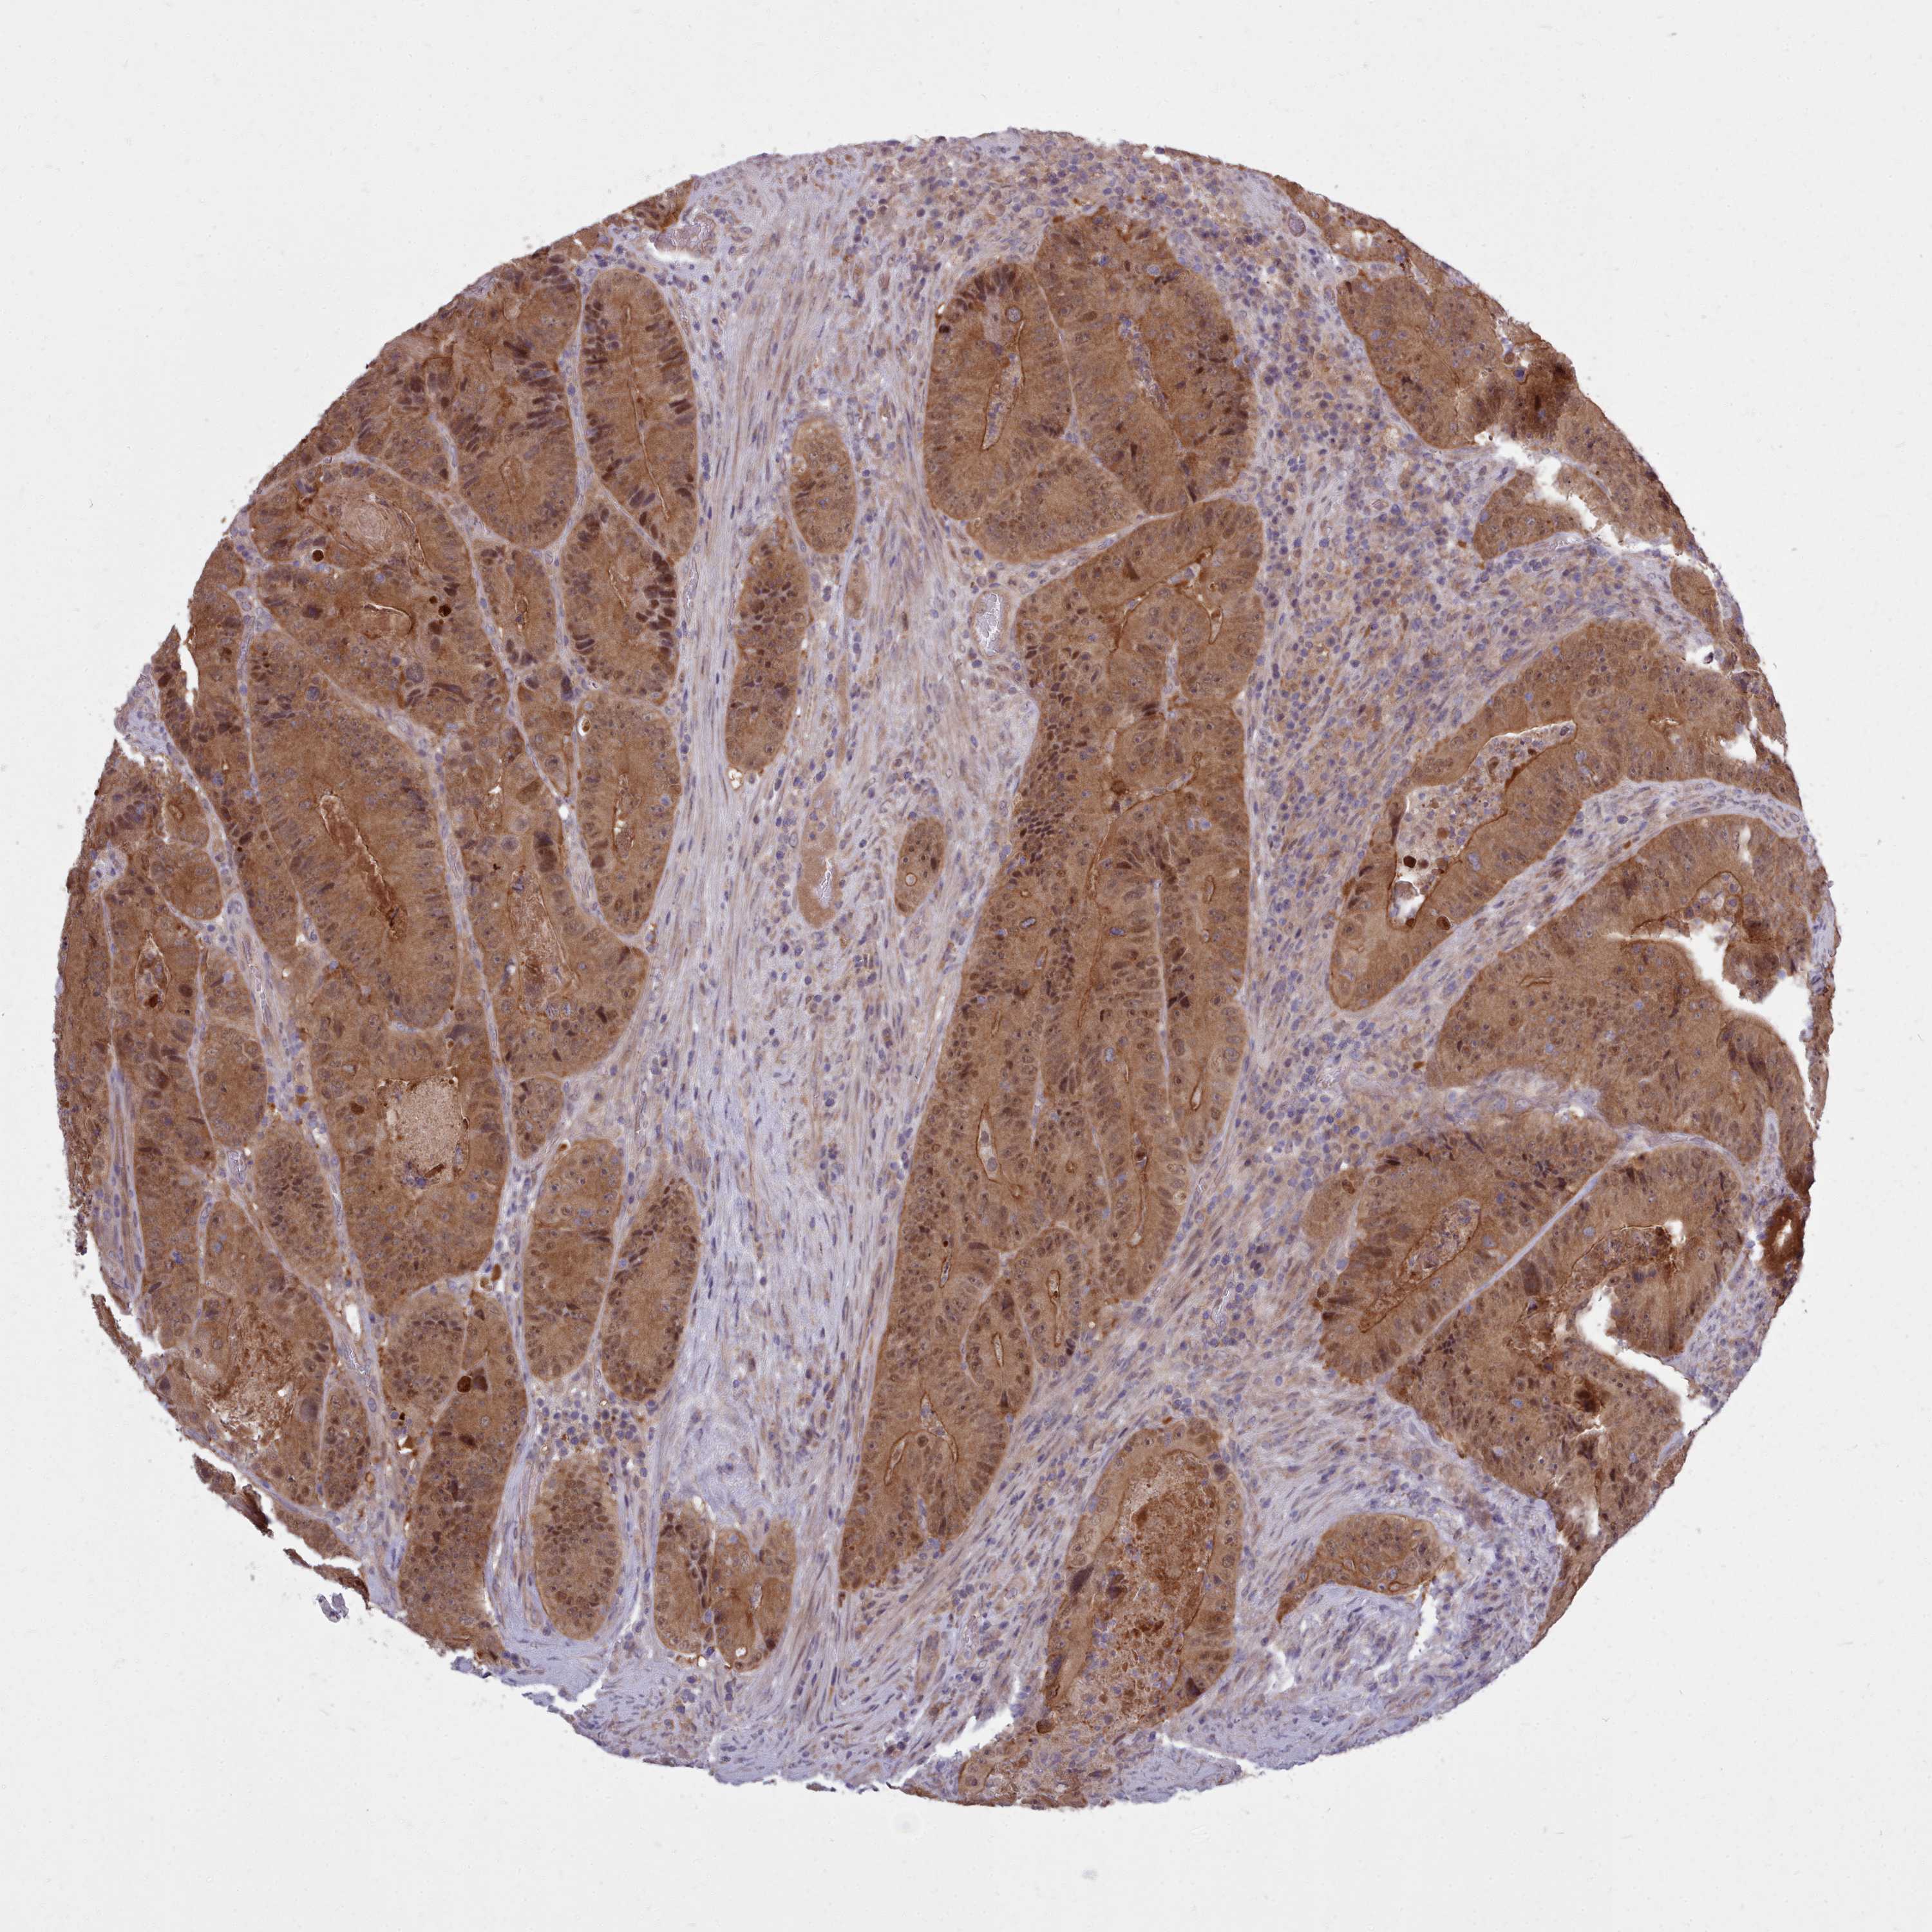

AHCY

CANCER COLORECTAL CANCER Show tissue menu

Colorectal cancer

Human cancer

Colon adenocarcinoma